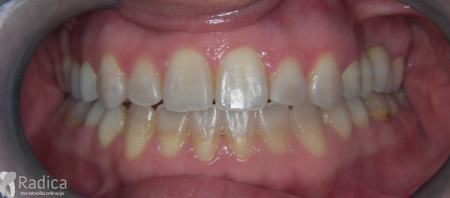

Slučaj 3: ispravljanje kompresije Invisalign full terapijom